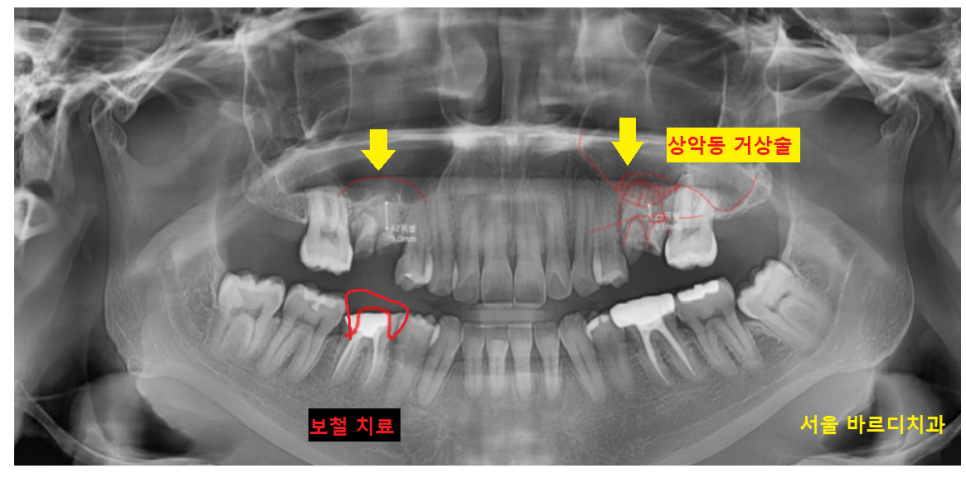

윗니 어금니의 경우 상악동이라는 구조물이 있는데

남아있는 잇몸뼈가 없는 경우

이 상악동을 들어 올려 뼈이식을 진행하여야합니다.

상악동을 들어올리고

뼈 이식을 한뒤

풍산동 임플란트가 필요했습니다.

24.03.30

풍산동 임플란트 상악동 올리고

뼈이식을 시행한 부위입니다.

돔 형태로 잘 이식이 되었습니다